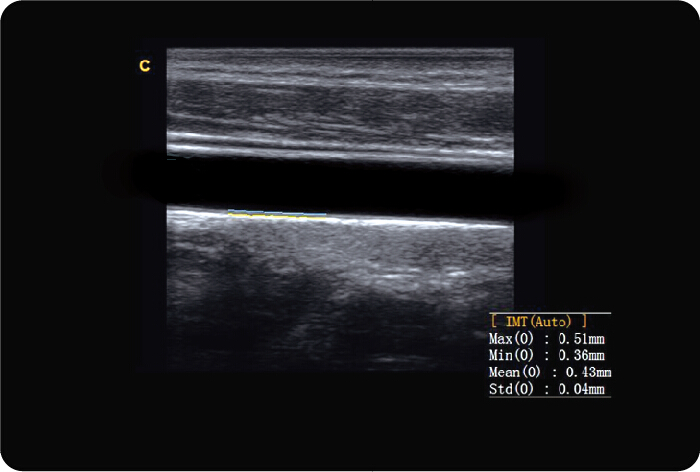

Función de IMT

Traza automáticamente la íntima, y mide el grueso de la íntima. Esto le permite medir la íntima más rápido, más fácil y con mayor precisión.